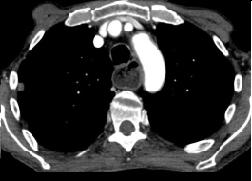

Un autre cas de cancer epidermoide du

1/3 moyen de oesophage avec metastase ganglionaire

pulmonaire . Bilan pre-therapeutique .

- Image TDM fenetre mediastinal en coupe

coronal ( frontale) et en coupe axiale a

traverse la tumeur . Image du tumeur de

oesophage avec extention locaux aortique et au

ganglions pulmonaires